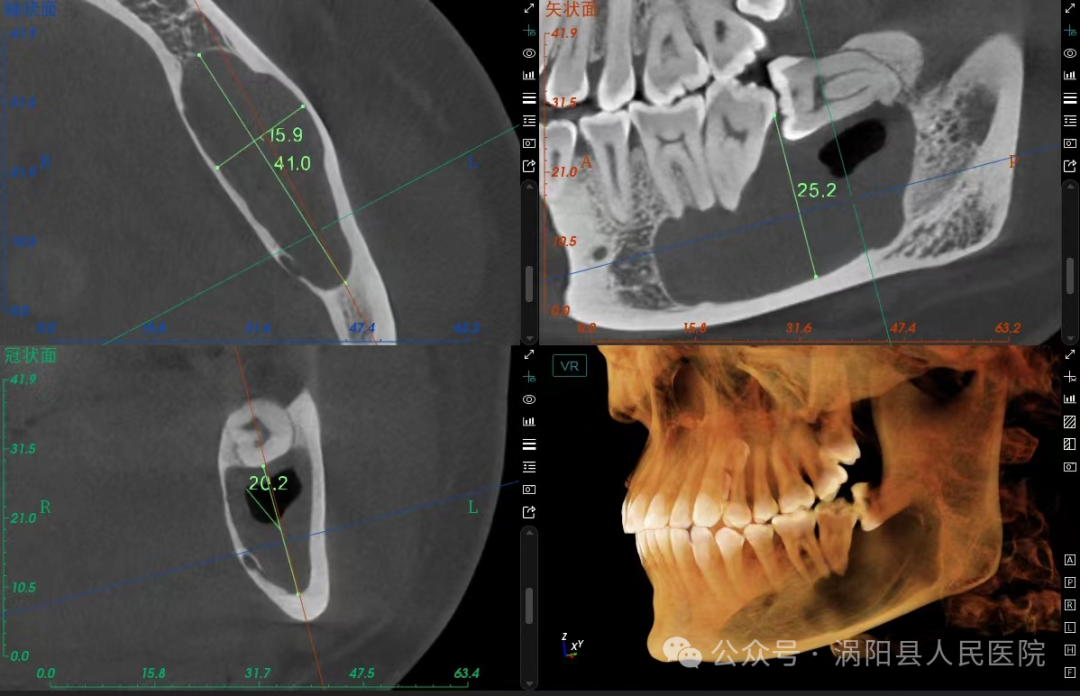

近日,30岁的刘女士因下颌智齿反复发炎至我院就诊,刘女士此前多次想要拔除这颗“惹祸”的智齿,但由于对拔牙过程中锤击等暴力操作的恐惧一直未能下定决心。门诊接诊的杨华一医生通过查看刘女士口内情况和牙片后发现该智齿不仅反复发炎,而且由于长年累月的食物嵌塞,下颌第二磨牙因牙周组织破坏已达到二度松动,如果不及时拔除该阻生智齿,下颌第二磨牙的脱落只是时间问题,甚至还可能引起颌骨囊肿等严重的并发症!